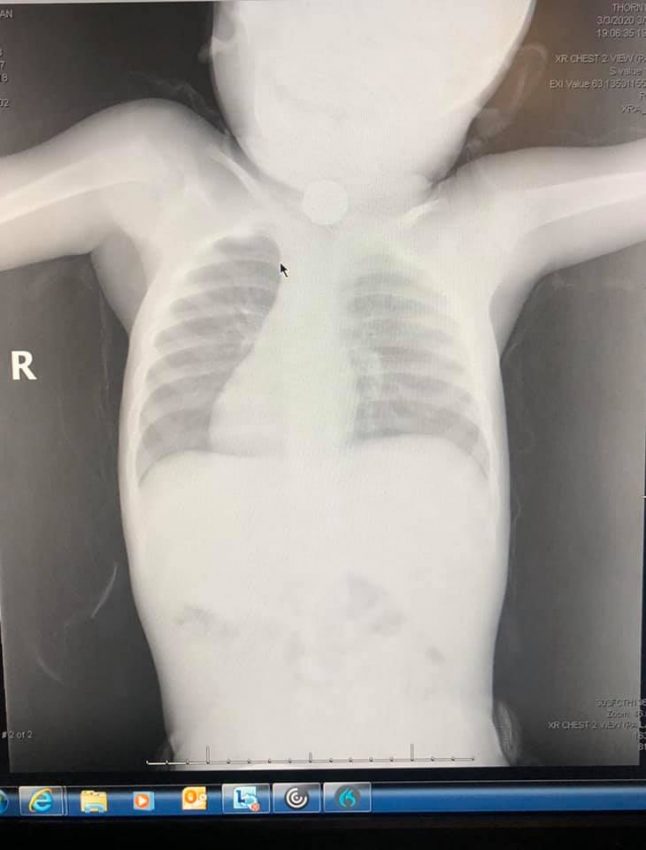

Ashley Mendez și copilul ei au ajuns la Urgențe cu Ambulanța, acolo unde copilului i s-a făcut o radiografie.

Inițial, chiar și medicii au fost convinși că este vorba de o monedă.

Totuși, la o privire mai atentă pe imaginile de la radiografie, situația avea să ia o întorsătură neașteptată.

„Când a ajuns pe mâna chirurgilor radiografia, aceștia ne-au întrebat dacă nu cumva băiatul nostru a avut acces la o baterie plată (gen buton) care este destul de mică. Eu și soțul ne uitam unul la altul și amândoi am răspuns imediat că nu, absolut deloc. Apoi mi-am amintit brusc de cântarul meu de bucătărie.